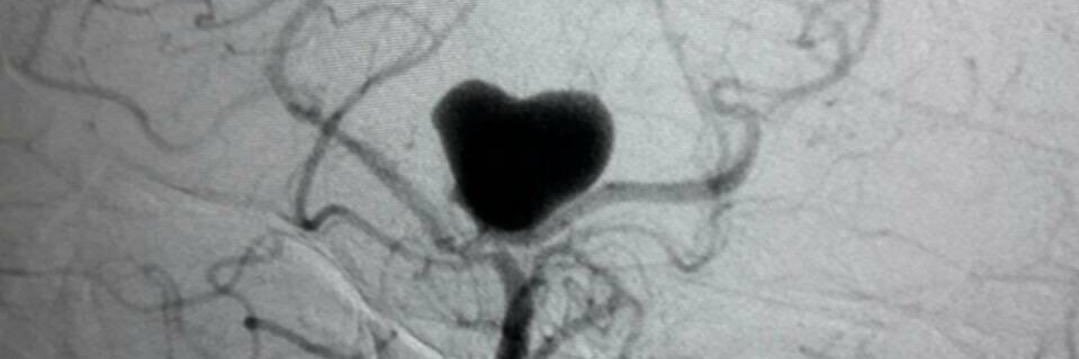

El Dr. Carlos Pérez@Justcharly9, nos resume en menos de 15 minutos los dos principales ensayos clínicos que comparan tratamiento Endovascular VS Quirúrgico (ISAT, IBRAT) de aneurismas rotos.